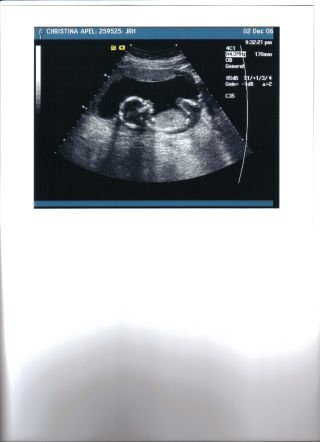

I'm back But i had alittle scary. I was spotting but it was nothing thank god. I just have alittle ireation in there. SO they just want me to take it easy. Baby is fine and healthy. She was trying to see if she could tell what it is she said it might be a but she thinks that it is the umbical cord was in the way. But is ok cause i get another on in a week to see what the sex is. Here is some pics of the baby. There is one that is so cute that it has it arms behind it head and knees are up. I see it on the seen moving around jumping and moving it arms legs. It was so cute. Image Attachment(s):

glad to hear you are ok! Wow look at his/her legs!! how cute!!